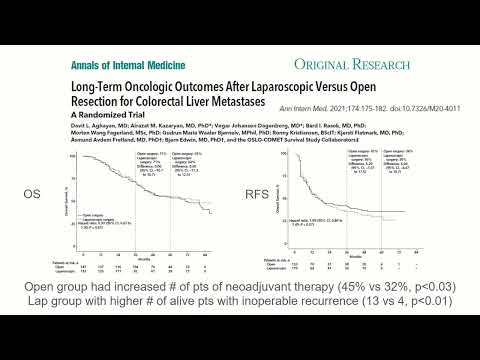

DEB02: Chemotherapy Should Always be Given Prior to Liver Surgery for CRLM? Pro/Con

Debate 02: Chemotherapy Should Always be Given Prior to Liver Surgery for CRLM? Pro/Con